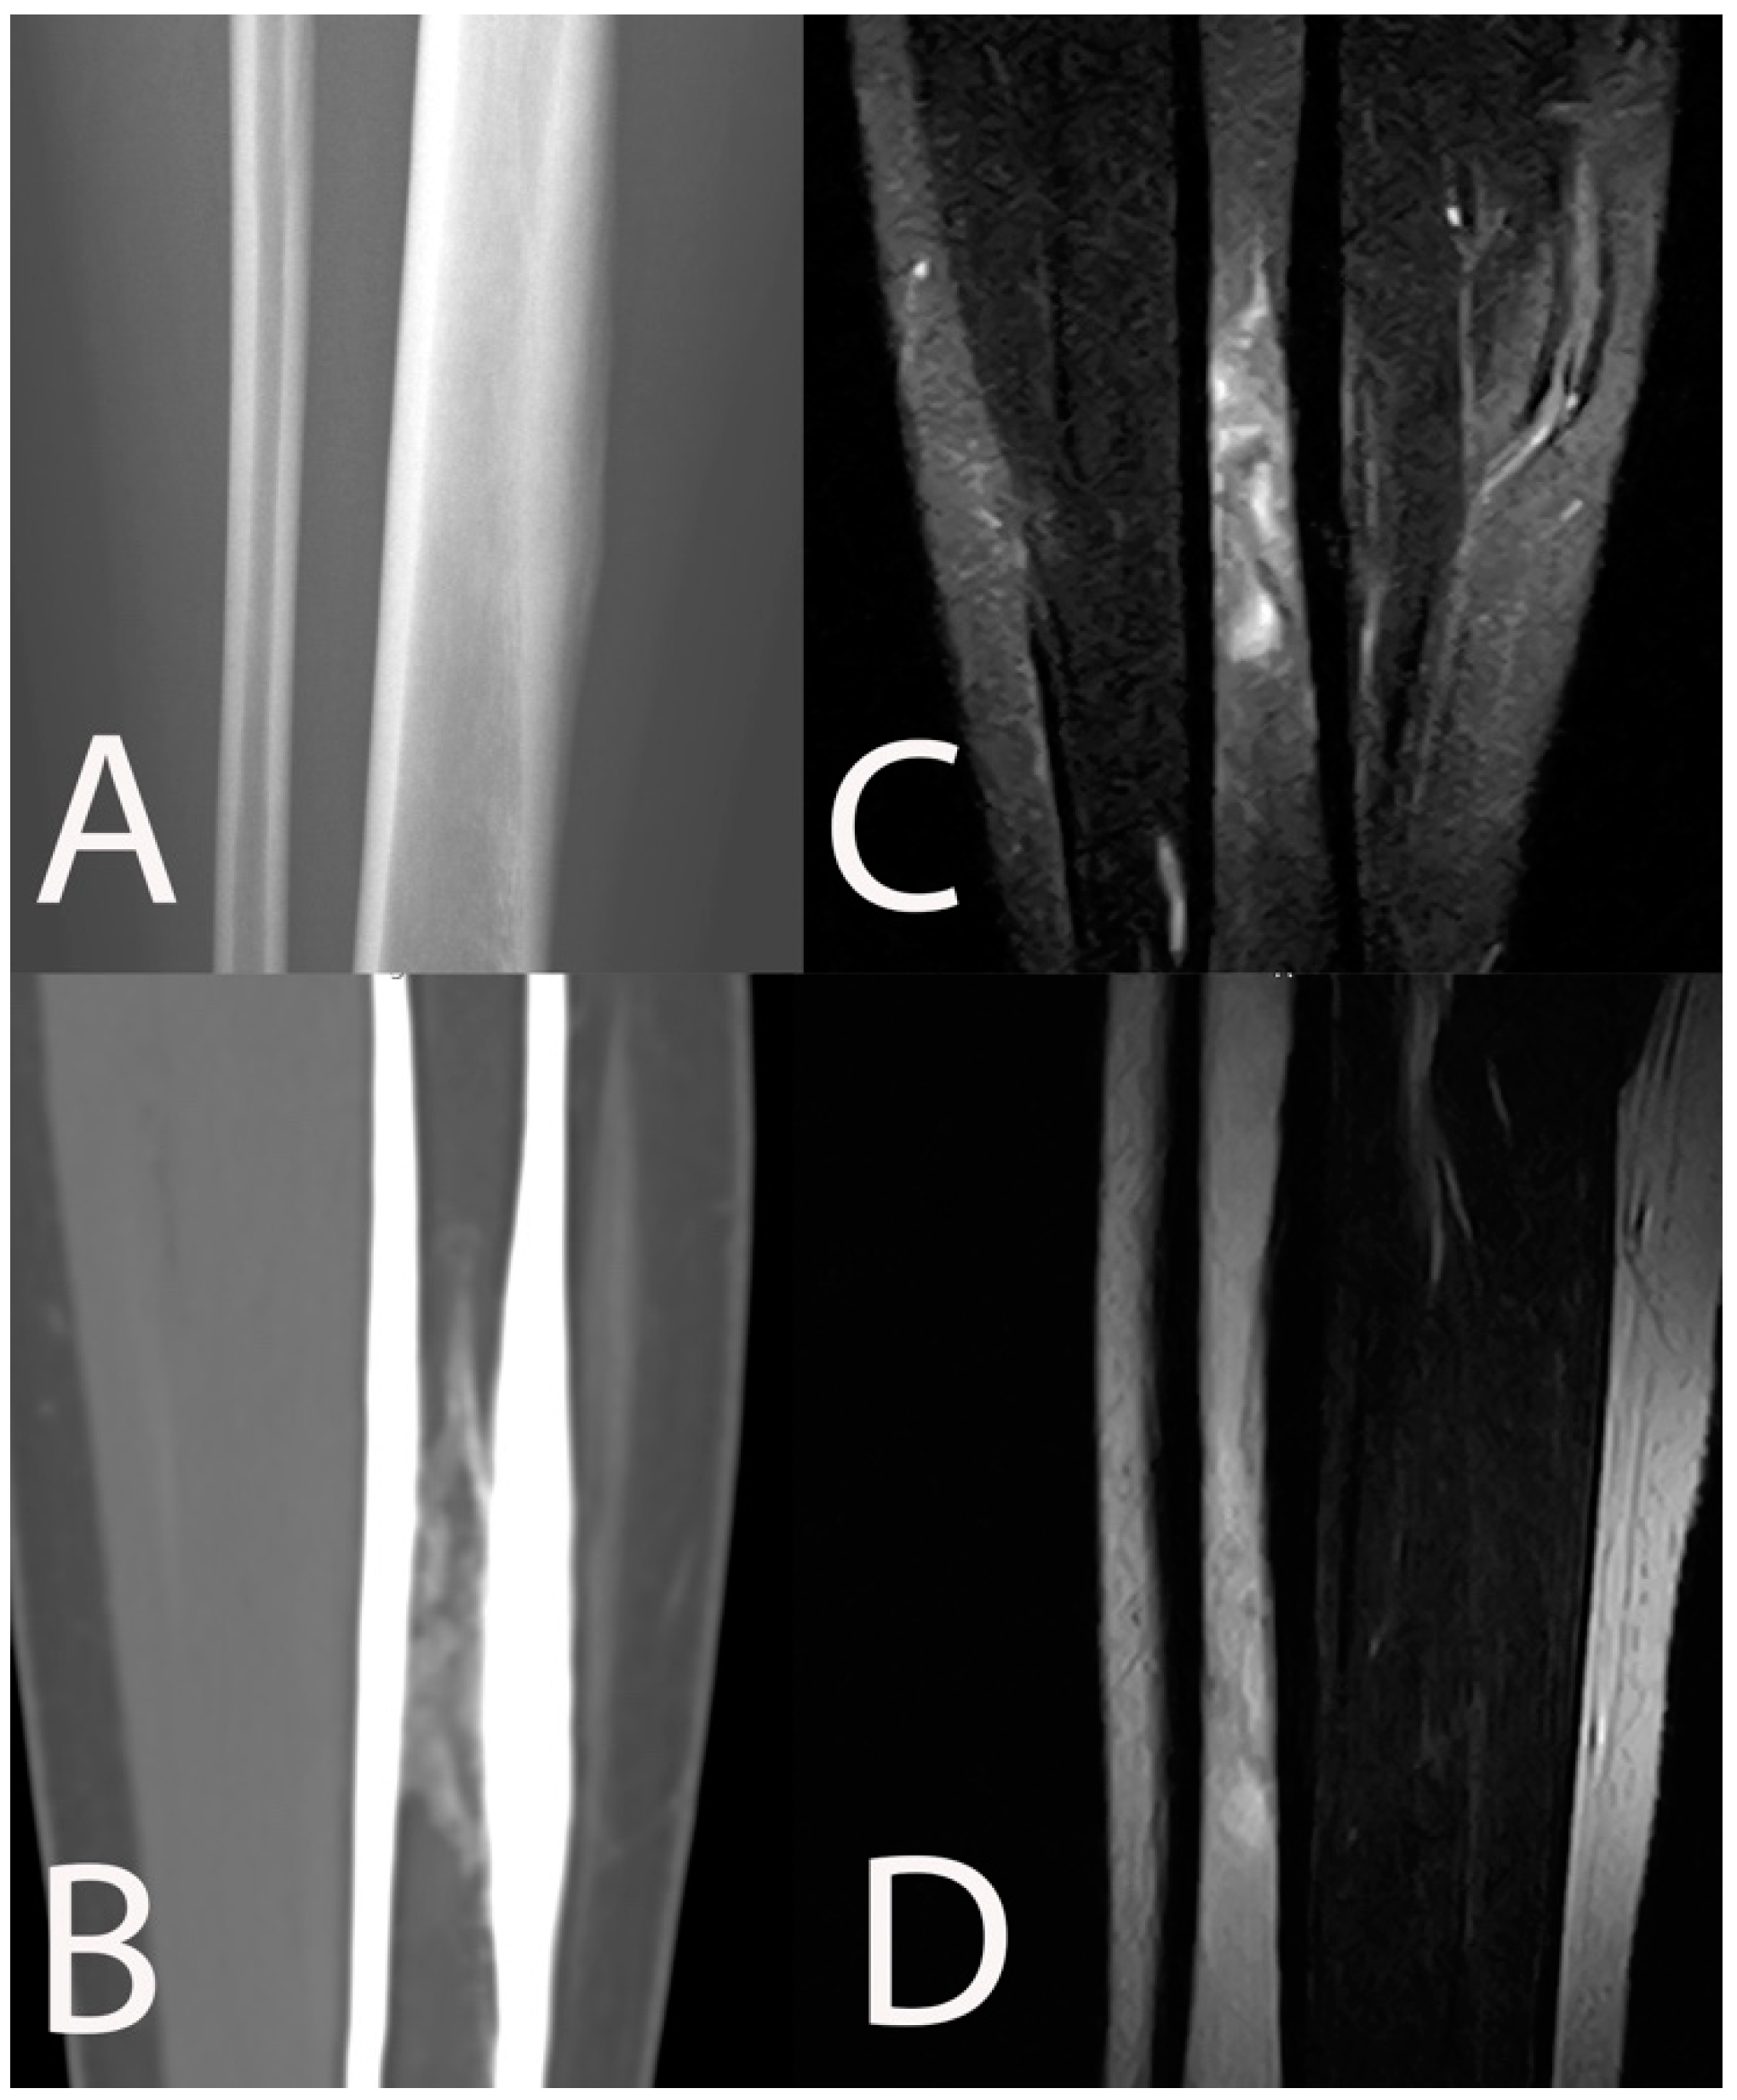

- Kaim, A.H.; Gross, T.; von Schulthess, G.K. Imaging of chronic posttraumatic osteomyelitis. Eur. Radiol. 2002, 12, 1193–1202. [Google Scholar] [CrossRef] [PubMed]

- Lee, Y.J.; Sadigh, S.; Mankad, K.; Kapse, N.; Rajeswaran, G. The imaging of osteomyelitis. Quant. Imaging Med. Surg. 2016, 6, 184–198. [Google Scholar] [CrossRef] [Green Version]

- Bühne, K.H.; Bohndorf, K. Imaging of posttraumatic osteomyelitis. Semin. Musculoskelet. Radiol. 2004, 8, 199–204. [Google Scholar] [CrossRef] [PubMed]